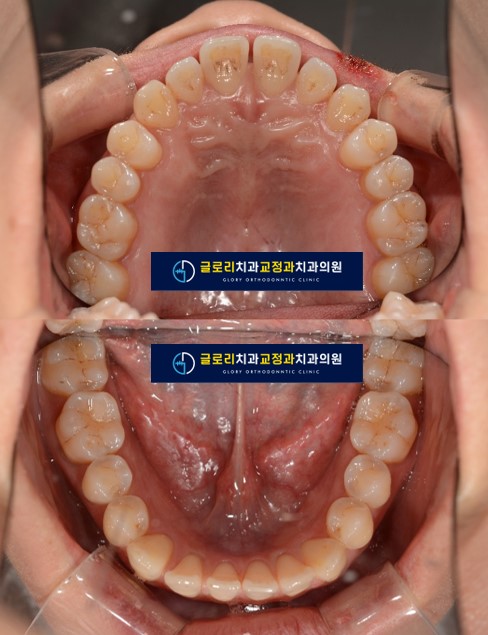

2) 교합면 사진

교합면에서도 어금니쪽은 촘촘하게 치아들이 붙어있지만

앞니쪽은 공간이 많이 있는 것을 알 수 있습니다.